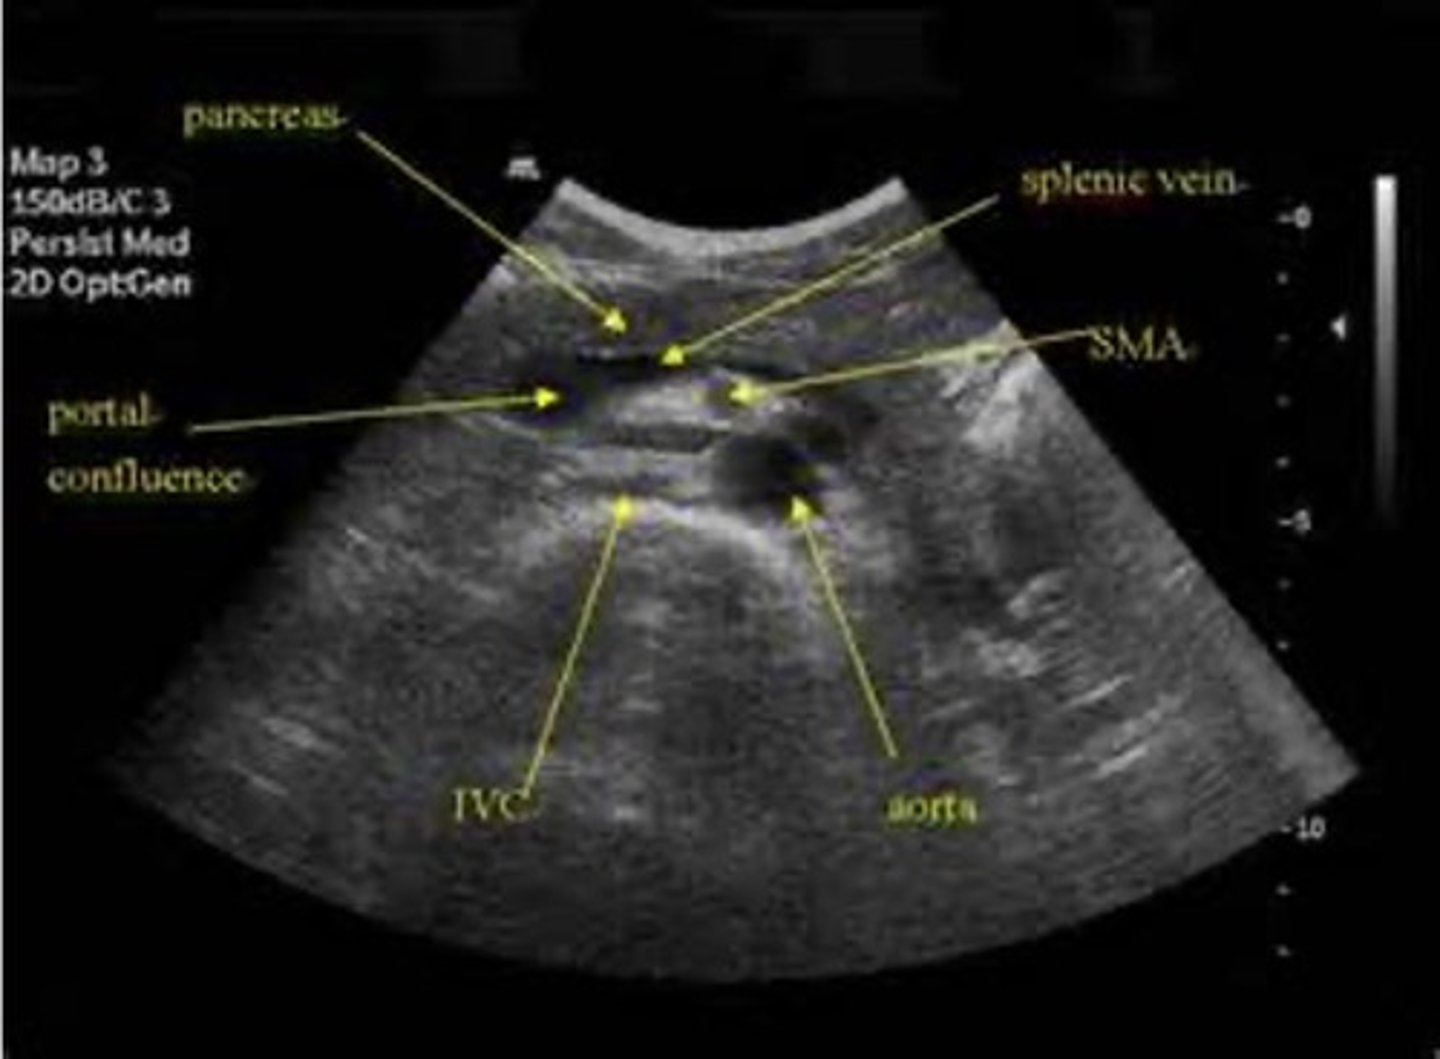

Normal pancreas

Normal pancreas US

Normal pancreas US (pic 2)